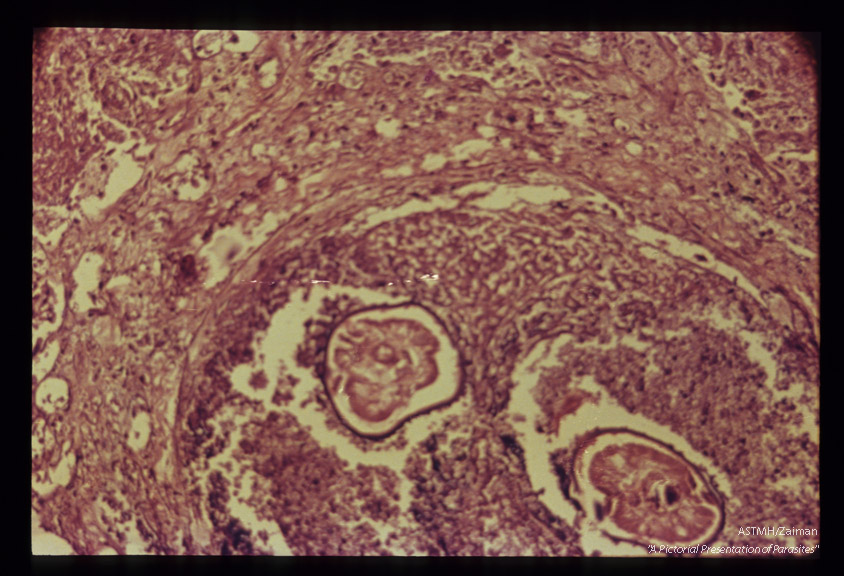

Lung nodule with cross section of filarial nematodes, probably adolescent Dirofilaria.

Description: Lung nodule with cross section of filarial nematodes, probably adolescent Dirofilaria.